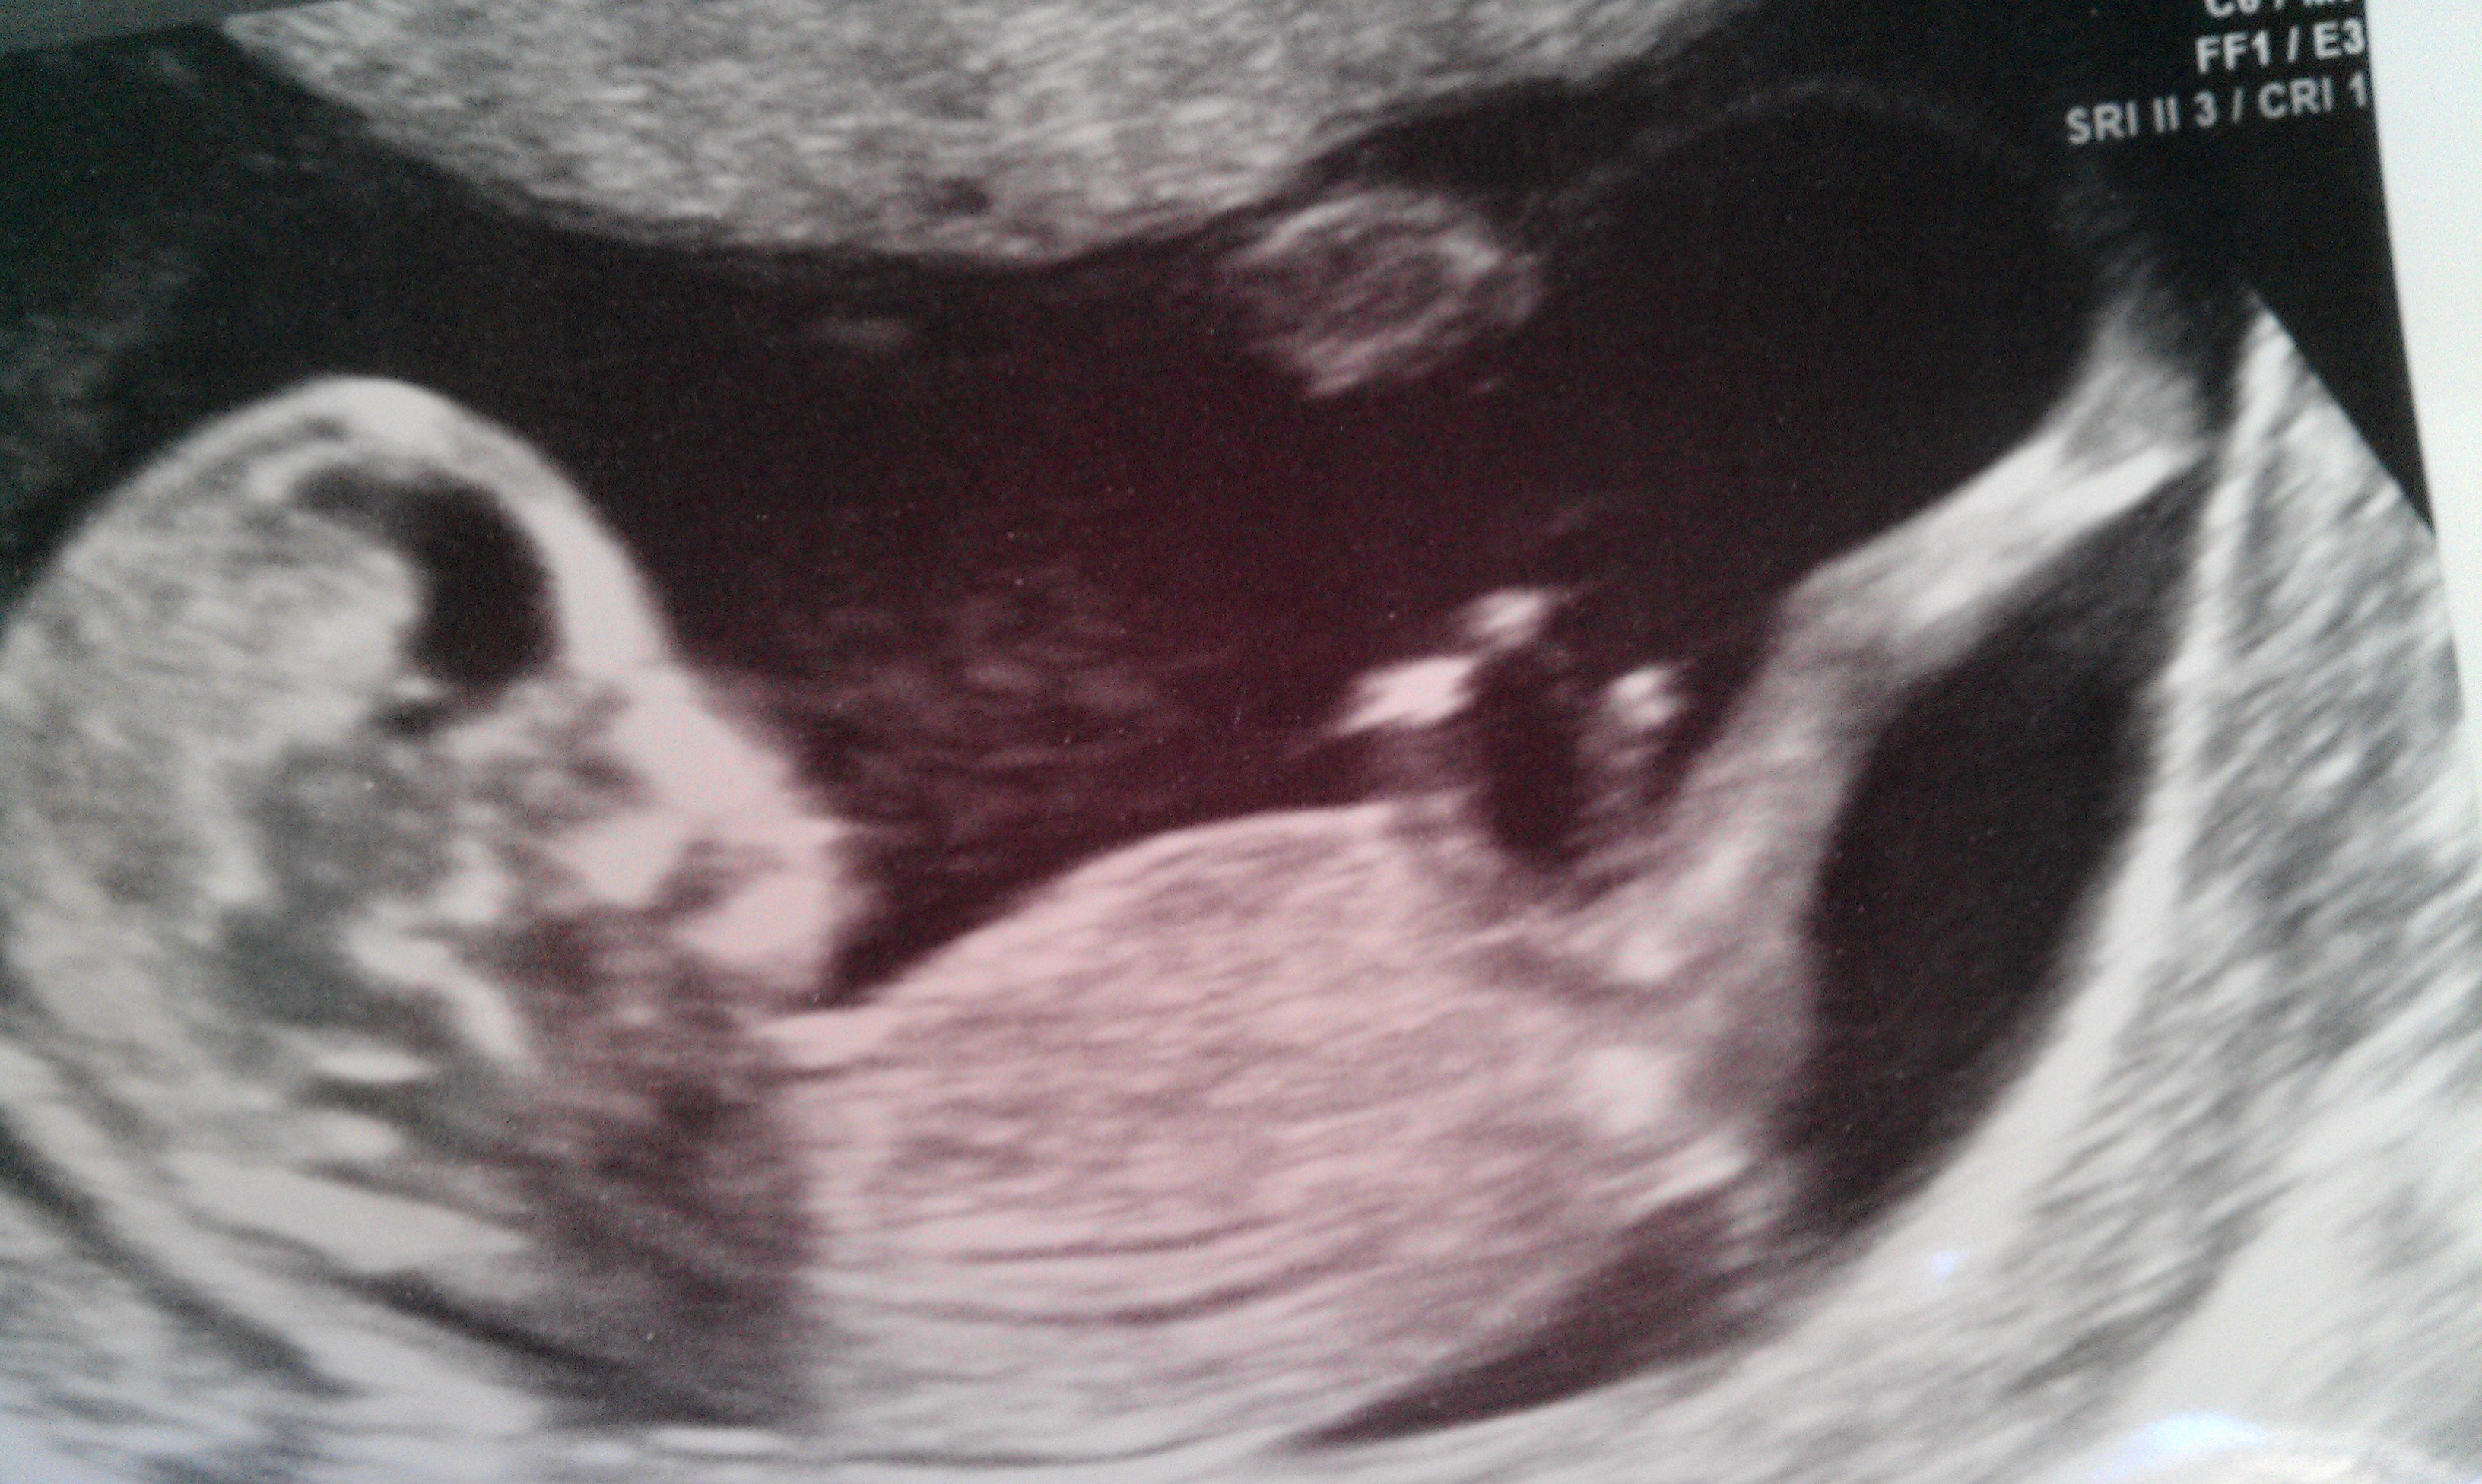

I think I can tell but am a bit confused by skull/nub theory so any help and your own guesses would be so appreciated! This scan was taken at 12 weeks and I still have 2 weeks to wait until 20 wk scan - seems like forever!!